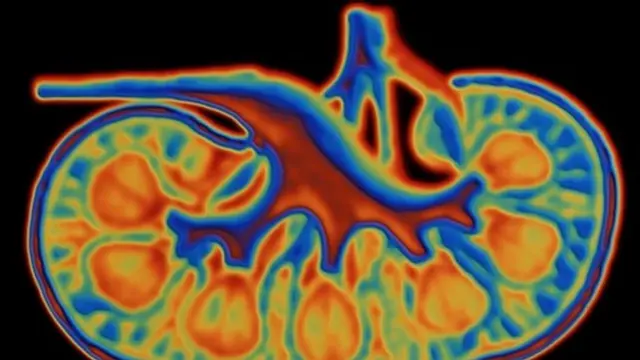

ጎንና ጎናችን ሥር የተሸጎጡት ሁለቱ ኩላሊቶቻችን የባቄላ ቅርጽ ነው ያላቸው።

በመጠን ደግሞ የኮምፒውተር "ማውዝ" ያክላሉ።

ከታችኛው የጎድን አጥንቶቻችን ውሸቅ ብለው በግራና በቀኝ ጎናችን የሚገኙ ጉደኛ ፍጥረቶች ናቸው።